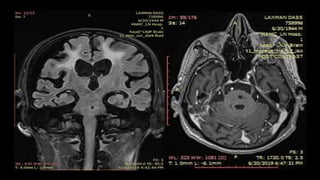

• #82 THIS IS THE SAGGITAL T1 W MRI BRAIN IMAGE SHOWING area of T1 HYPOINTENSITY IN CORONA RADIATA REGION

• #83 This is the Axial t2wi of the same pt showing hyperintense signal corresponds to the right corona radiate region

• #84  These are the axial T2WI taken at sequential intervals of a patient with R MCA territory infarct showing T2 fogging phenomenon with decrease in the the signal intensity over the period of time almost reaching to isointensity in 3rd image

• #85 CORONAL FLAIR IMAGE OF THE SAME PT SHOWS HYPERINTENSE SIGNAL

• #87 Axial T1 WI, t2 and flair SHOWS ill defined hypointense signal, apeearing hyperintense on T2/FLAIR in left mca territory ,